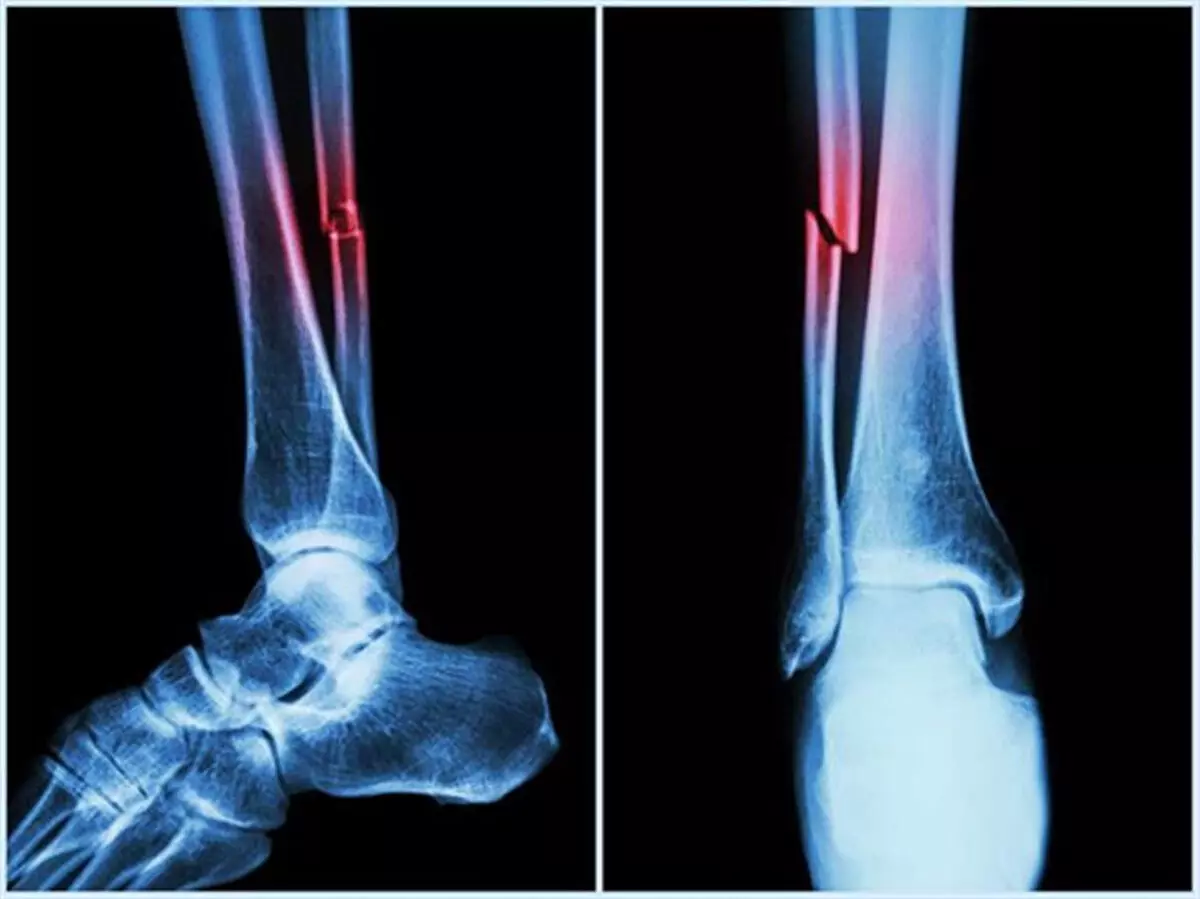

यह शोध बायोकेमिस्ट्री पत्रिका में प्रकाशित हुआ है। इसके परिणामों का उपयोग हड्डियों और कार्टिलेज पुनर्जनन के उन्नत उपचारों, बेहतर प्रत्यारोपण और अधिक प्रभावी प्रोटीन-आधारित दवाओं के लिए किया जा सकता है।

इस संदर्भ में एनआईटी की टीम ने कहा कि बोन मॉर्फोजेनेटिक प्रोटीन-2 (बीएमपी-2) हड्डियों और कार्टिलेज के निर्माण, चोटों को ठीक करने और स्टेम कोशिकाओं को अस्थि-निर्माण कोशिकाओं में बदलने में अहम भूमिका निभाता है।

शोध से प्राप्त जानकारी अस्थि भंग, रीढ़ की हड्डी की चोटों और अपक्षयी अस्थि रोगों के उपचार के लिए बेहतर जैव पदार्थ और दवा वितरण प्रणाली विकसित करने में मदद कर सकता है। यह उपचार के दौरान दवा वितरण को अनुकूलित करने और रोगियों के लिए दुष्प्रभावों को कम करने में भी सहायक हो सकता है।